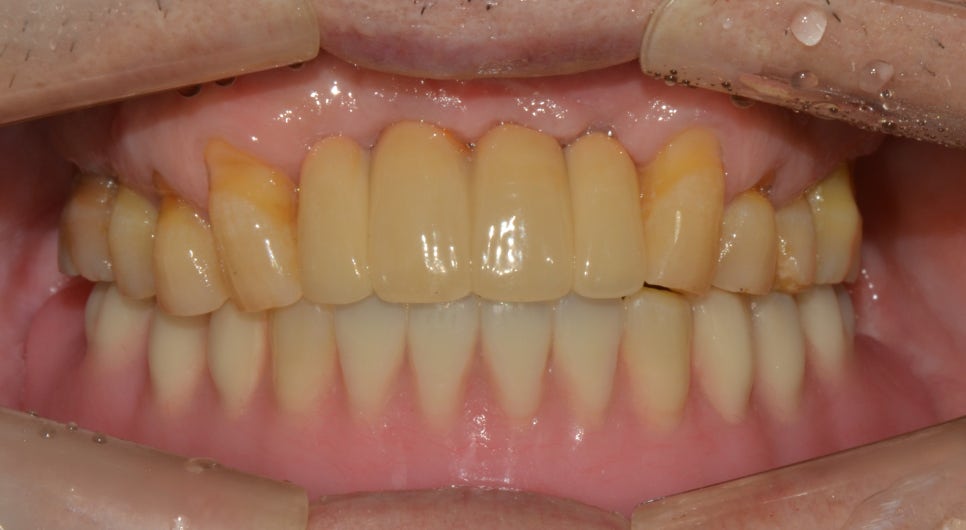

치료 후

2020년 4월 1일

치료 진행

검진을 하였을 때 구강 위생 상태가 좋지 않아 앞서 말씀드린 것과 같이 전체적으로 이가 흔들리고 있었습니다. 그리고 건강상의 이유로 수술을 최소한으로 하고 싶으시다고 말씀해 주셔서 하악은 전악발치 후 틀니, 상악은 전치부 발치 후 임플란트 2개를 식립하고 브릿지로 연결하여 치료를 진행해 주었는데요. 이 때 발치를 진행한 후에는 잇몸치유 과정을 기다린 후 하악 틀니와 교합을 맞춰 상악 보철을 진행하였습니다. 치료 후에는 더 이상 치아 흔들림이 없으면서 저작력도 많이 회복되어 식사를 하는 것에 있어서 편하다고 좋아해 주셨습니다^^